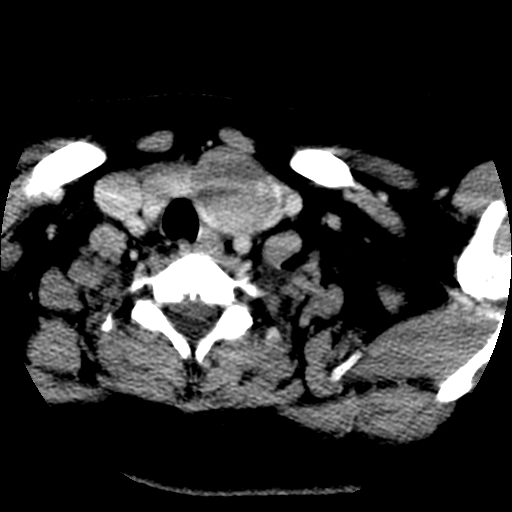

标题: CT25491:女,55岁,发现左侧甲状腺肿块一个月。 [打印本页]

标题: CT25491:女,55岁,发现左侧甲状腺肿块一个月。

女,55岁,发现左侧甲状腺肿块一个月,彩超示:甲状腺多发结节伴左叶结节液化。

考虑右叶结节性甲状腺肿,伴左叶钙化。主要(1)密度均匀,边境清。(2)病灶与血管界限清。

边界清,无明显强化,考虑考虑甲状腺腺瘤